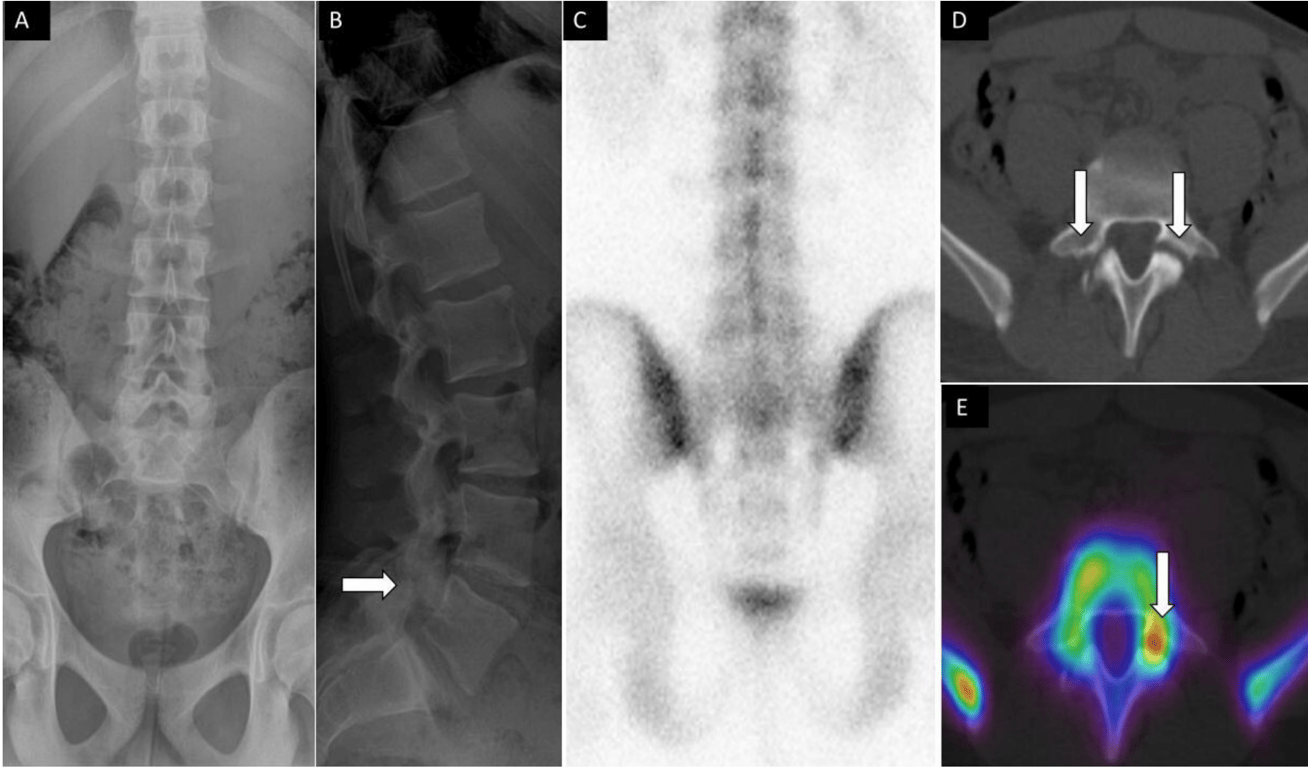

71-year-old woman with low back, buttock, and bilateral leg pain. Lateral (A) spine radiograph shows L4 to L5 instrumentation with prior interspinous spacer and unilateral pedicle screws with interbody device (arrow) without evidence of complications. Lumbar spine T2 sagittal magnetic resonance image (B) shows no central canal stenosis, also seen on axial (not displayed) and metal artifact at L4 to L5 (arrow) related to instrumentation. Posterior planar 99mTc-MDP bone scan (C) and axial fused single photon emission computed tomography with computed tomography (D) images show H-shaped radiotracer uptake within the sacrum, with associated sclerotic changes on computed tomography (E), compatible with sacral insufficiency fracture.